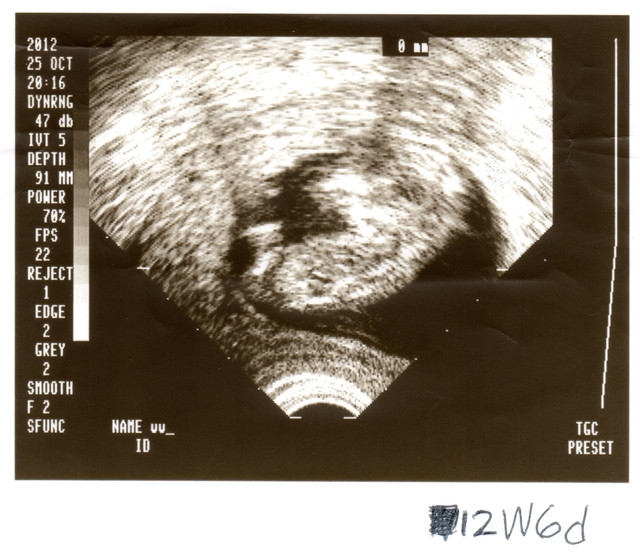

由於我有一個很貴的寶寶

又是努力很久打很多針才有的

所以一旦確認懷孕後